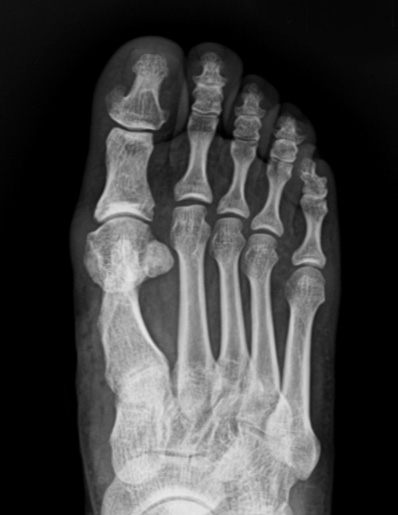

4세대 MICA 수술법

최소 침습적

무지외반 교정술

작은 구멍을 통해 초음파 절골기를 이용하여 뼈를 절골합니다.

4세대 MICA 방법을 이용하면 개방적 방법만큼의 각 교정도 가능하기 때문에

중등도 이상의 큰 각도의 무지외반증에도 충분히 적용이 가능합니다.